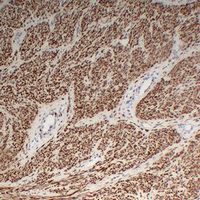

(Immunohistochemical analysis of Desmin staining in human fibroid formalin fixed paraffin embedded tissue section. The section was pre-treated using heat mediated antigen retrieval with sodium citrate buffer (pH 6.0). The section was then incubated with the antibody at room temperature and detected using an HRP conjugated compact polymer system. DAB was used as the chromogen. The section was then counterstained with haematoxylin and mounted with DPX.)